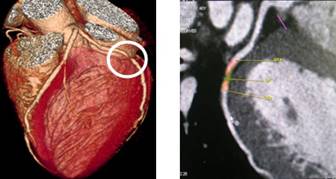

320排螺旋CT具备16cm宽覆盖探测器,实现动态容积扫描,360度的各向同性采集能力及[email protected]%密度分辨率的量子探测器,一次心跳全心脏采集,一圈扫描器官成像,一次检查完成多重任务,实现真正的动态容积体灌注及心脏、神经一站式检查;西门子Flash炫速CT扫描系统,具备两套同时旋转的X射线球管及探测器,实现了43cm/s的极快CT扫描速度和75 ms的时间分辨率,完成全胸扫描仅需0.6秒,使得患者做心脏扫描时无须食用β-受体阻滞药,亦无须屏气,并可实现低于1mSv的超低辐射剂量,配置第二代双能量、宽151级纯化能谱,组织鉴别能力进一步提高,可开展多达10余种双能量成像应用。

头颅一站式检查:320排容积CT覆盖范围达16cm,球管旋转一周可以覆盖整个脑组织,获得全脑0.5mm层厚各向同性全脑信息。一次扫描可以获得平扫容积图像、以时间为序列全脑动态3D-CTA图像(包括纯动、静脉期成像)及全脑灌注图像。一次检查即可排除脑出血、动脉瘤、动脉狭窄、梗塞、脑实质供血异常等多种病变及进行脑卒中筛查。